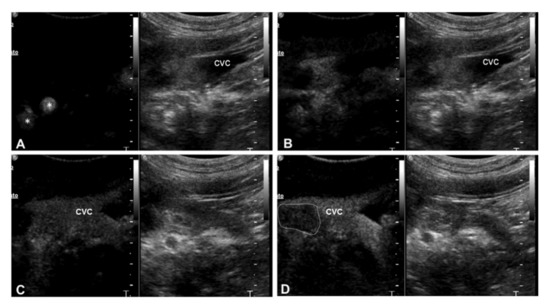

| 3 | Right adrenal carcinoma | Caudal vena cava | 1 Heterogeneous partially hyperechoic nodule with acoustic shadowing on the right adrenal gland (2.9 cm) | Intravascular homogeneous mass in contiguity with the primary tumor | Residual flow within the lumen of the vessel | Present | Heterogeneous | Irregular and ill-defined | Earlier | N/A |

| 4 | Right adrenal carcinoma | Caudal vena cava | Heterogeneous partially hyperechoic right adrenal gland with acoustic shadowing (width 1.5 cm) | Intravascular homogeneous mass with vessel distension | Residual flow within the lumen of the vessel | Present | Heterogeneous | Irregular and ill-defined | Earlier | N/A |

| 5 | Right adrenal pheochromocytoma | Caudal vena cava | 1 Heterogeneous mass on the right adrenal gland (5 cm) | Intravascular homogeneous mass with vessel distension | Residual flow within the lumen of the vessel | Present | Heterogeneous | Regular and well-defined | Earlier | Simultaneous |

| 6 | Left adrenal pheochromocytoma | Caudal vena cava | Heterogeneous left adrenal gland (width 2.3 cm) | Intravascular homogeneous mass with vessel distension | Residual flow within the lumen of the vessel | Present | Heterogeneous | Irregular and ill-defined | Earlier | N/A |

| 7 | Retroperitoneal liposarcoma | Caudal vena cava | Heterogeneous mass on the left retroperitoneal space, involving the left adrenal gland (3.5 cm) | Intravascular homogeneous mass | Intralesional Doppler signal; residual flow within the lumen of the vessel | Present | Heterogeneous | Irregular and ill-defined | Earlier | NA |